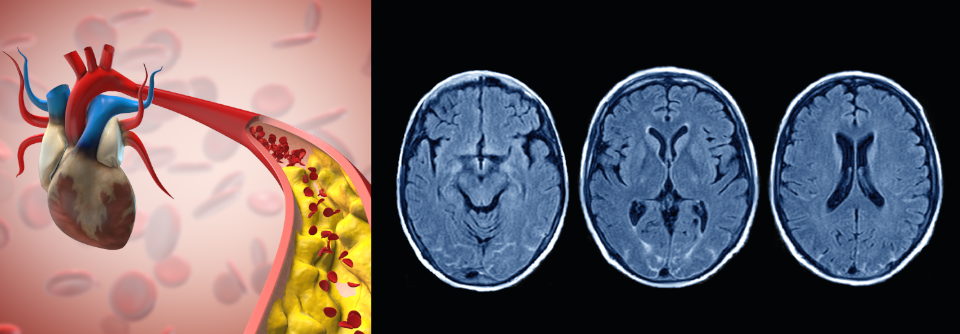

Die Prognose der peripheren arteriellen Verschlusskrankheit bleibt schlecht. Trotz aller Innovationen geht die Rate der Major-Amputationen nicht zurück. Dabei ließen sich schon mit einer Intensivierung der konservativen Therapie wesentliche Verbesserungen erreichen.

Eine intensivierte antithrombotische Therapie z.B. mit ASS plus Clopidogrel, vermag den Revaskularisations- und Amputationsbedarf bei Patienten mit peripherer arterieller Verschlusskrankheit signifikant zu senken. Allerdings wird dieser Erfolg mit einem erhöhten Blutungsrisiko erkauft, wie Professor Dr. Christine Espinola-Klein von der Universitätsmedizin Mainz ausführte.